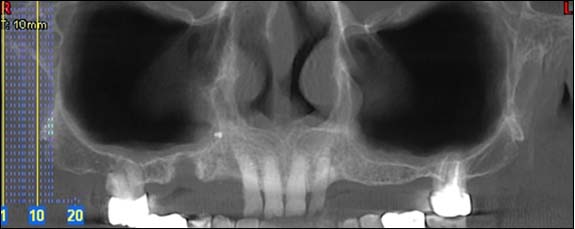

TÉLÉRADIOGRAPHIE DE PROFIL ET DE FACE :